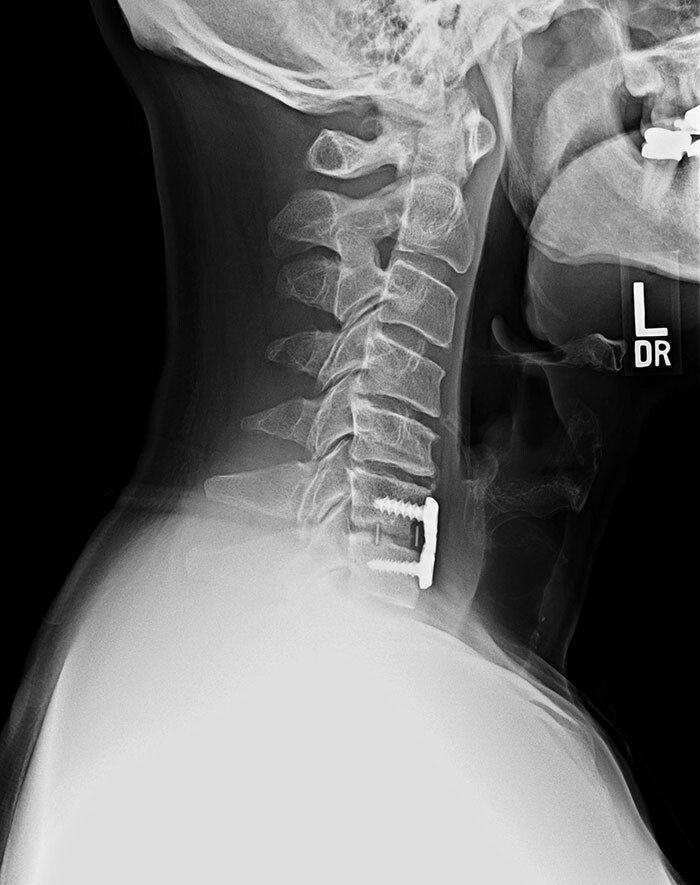

Контейнер с недоразвившимися костными клетками и стволовыми клетками, вставленный в шею пациента для регенерации позвоночника